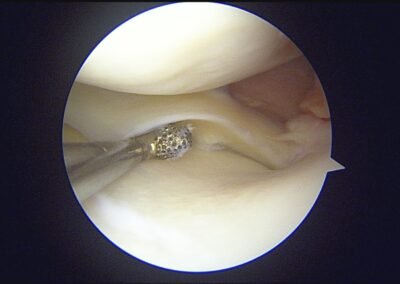

GalleryShoulder rotator cuff repair Meniscus root repair Meniscus repair Bankart repair for recurrent shoulder dislocation ACL reconstruction Machines Instruments